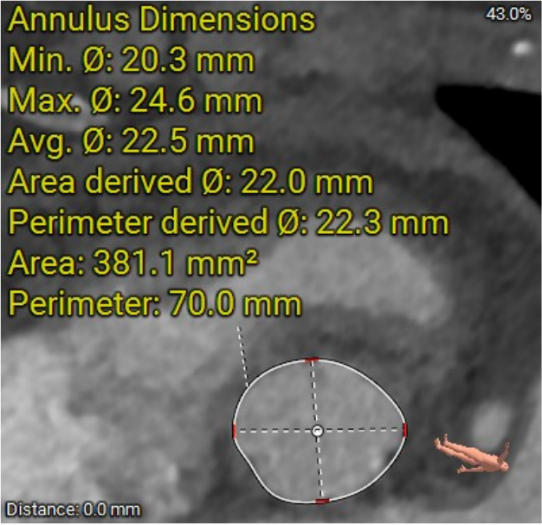

患者冠脉存在狭窄,TAVR术前首先进行冠脉处理。由于患者主动脉根部结构较小,左冠开口低,合并瓣叶增厚增长,植入人工瓣膜将存在冠脉阻塞风险,造成严重的手术并发症。经过分析讨论,术者决定瓣膜植入前对左侧冠脉进行预保护。